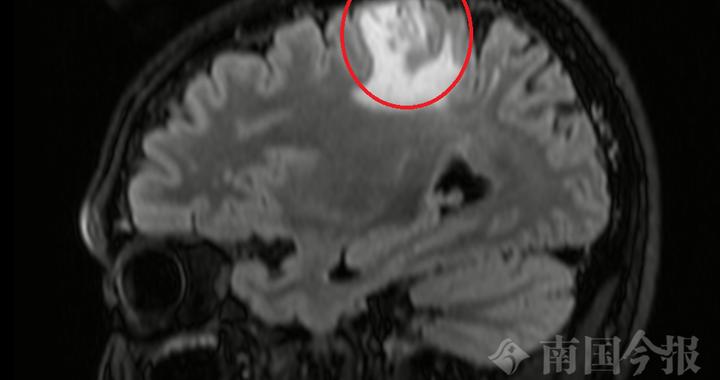

脑袋里“挖”出8厘米活虫!这个“土方子”害人不浅,很多人还在用! 最终医生在影像中发现关键线索:病灶会“移动”,还留下了“隧道”痕迹——这是虫子在脑里爬行的罪证。开颅手术后医生成功捕获一条8厘米长的活虫:裂头蚴被称为会“打隧道”的寄生虫图源:百度百科图中长得很像金针菇的虫子就是裂头蚴是曼氏迭宫绦虫的幼虫阶段裂头蚴是怎样生存的... 2026-05-12 13:22:00